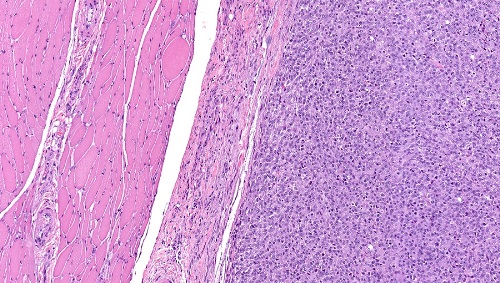

Патологическое состояние относится злокачественное новообразование, которое разрастается из поперечно-полосатой мышечной ткани. Местом локализации в организме может быть разные участки тела. При этом патологическом состоянии мышечные клетки приобретают разнообразную форму, вытягиваются либо округляются, клеточное ядро становится большим и приобретает яркую окраску. Происходит изменение свойств мышечной ткани в виде потери структуры, приобретает внешнее сходство с рабдомиомиобластами – эмбриональными клетками, которые впоследствии формируют мышечную ткань плода.

- Эмбриональная форма выполнена округлыми либо веретеновидными патологически трансформированными миоцитами с наличием несильной исчерченности. Эта форма самая распространенная у детей и подростков. Локализуется в основном в области верхней челюсти, носоглотке, шее, мочеполовой системе. Жизненный прогноз крайне неблагоприятный.